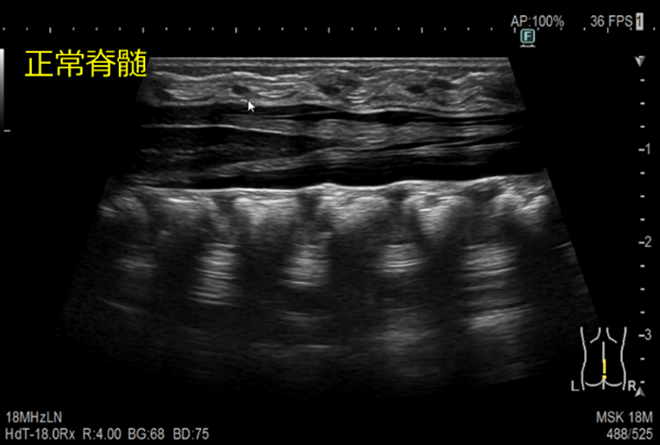

脊髄超音波検査

背中から超音波をあてて、脊髄病変の有無や性状の観察をします。

- 年齢が進んでくると観察しづらくなります。

- 検査時は、横を向いて背中を丸めた体勢を取って頂きます。

保護者の方に体勢保持の御協力をお願いしています。

年齢によっては、膝を抱えてうつ伏せの体勢でも行います。 - 初回の検査では、お洋服はおむつも含めて全て脱いで検査させて頂きます。

脊髄嚢胞瘤とは

髄液腔(拡大した脊髄中心管)が脊椎管外へ脱出する奇形のことです。

脂肪脊髄髄膜瘤とは

神経管閉鎖時に脊髄の背尾側に迷入発生する過誤腫性の奇形のことです。潜在性二分脊椎の原因の中で最も多い疾患です。